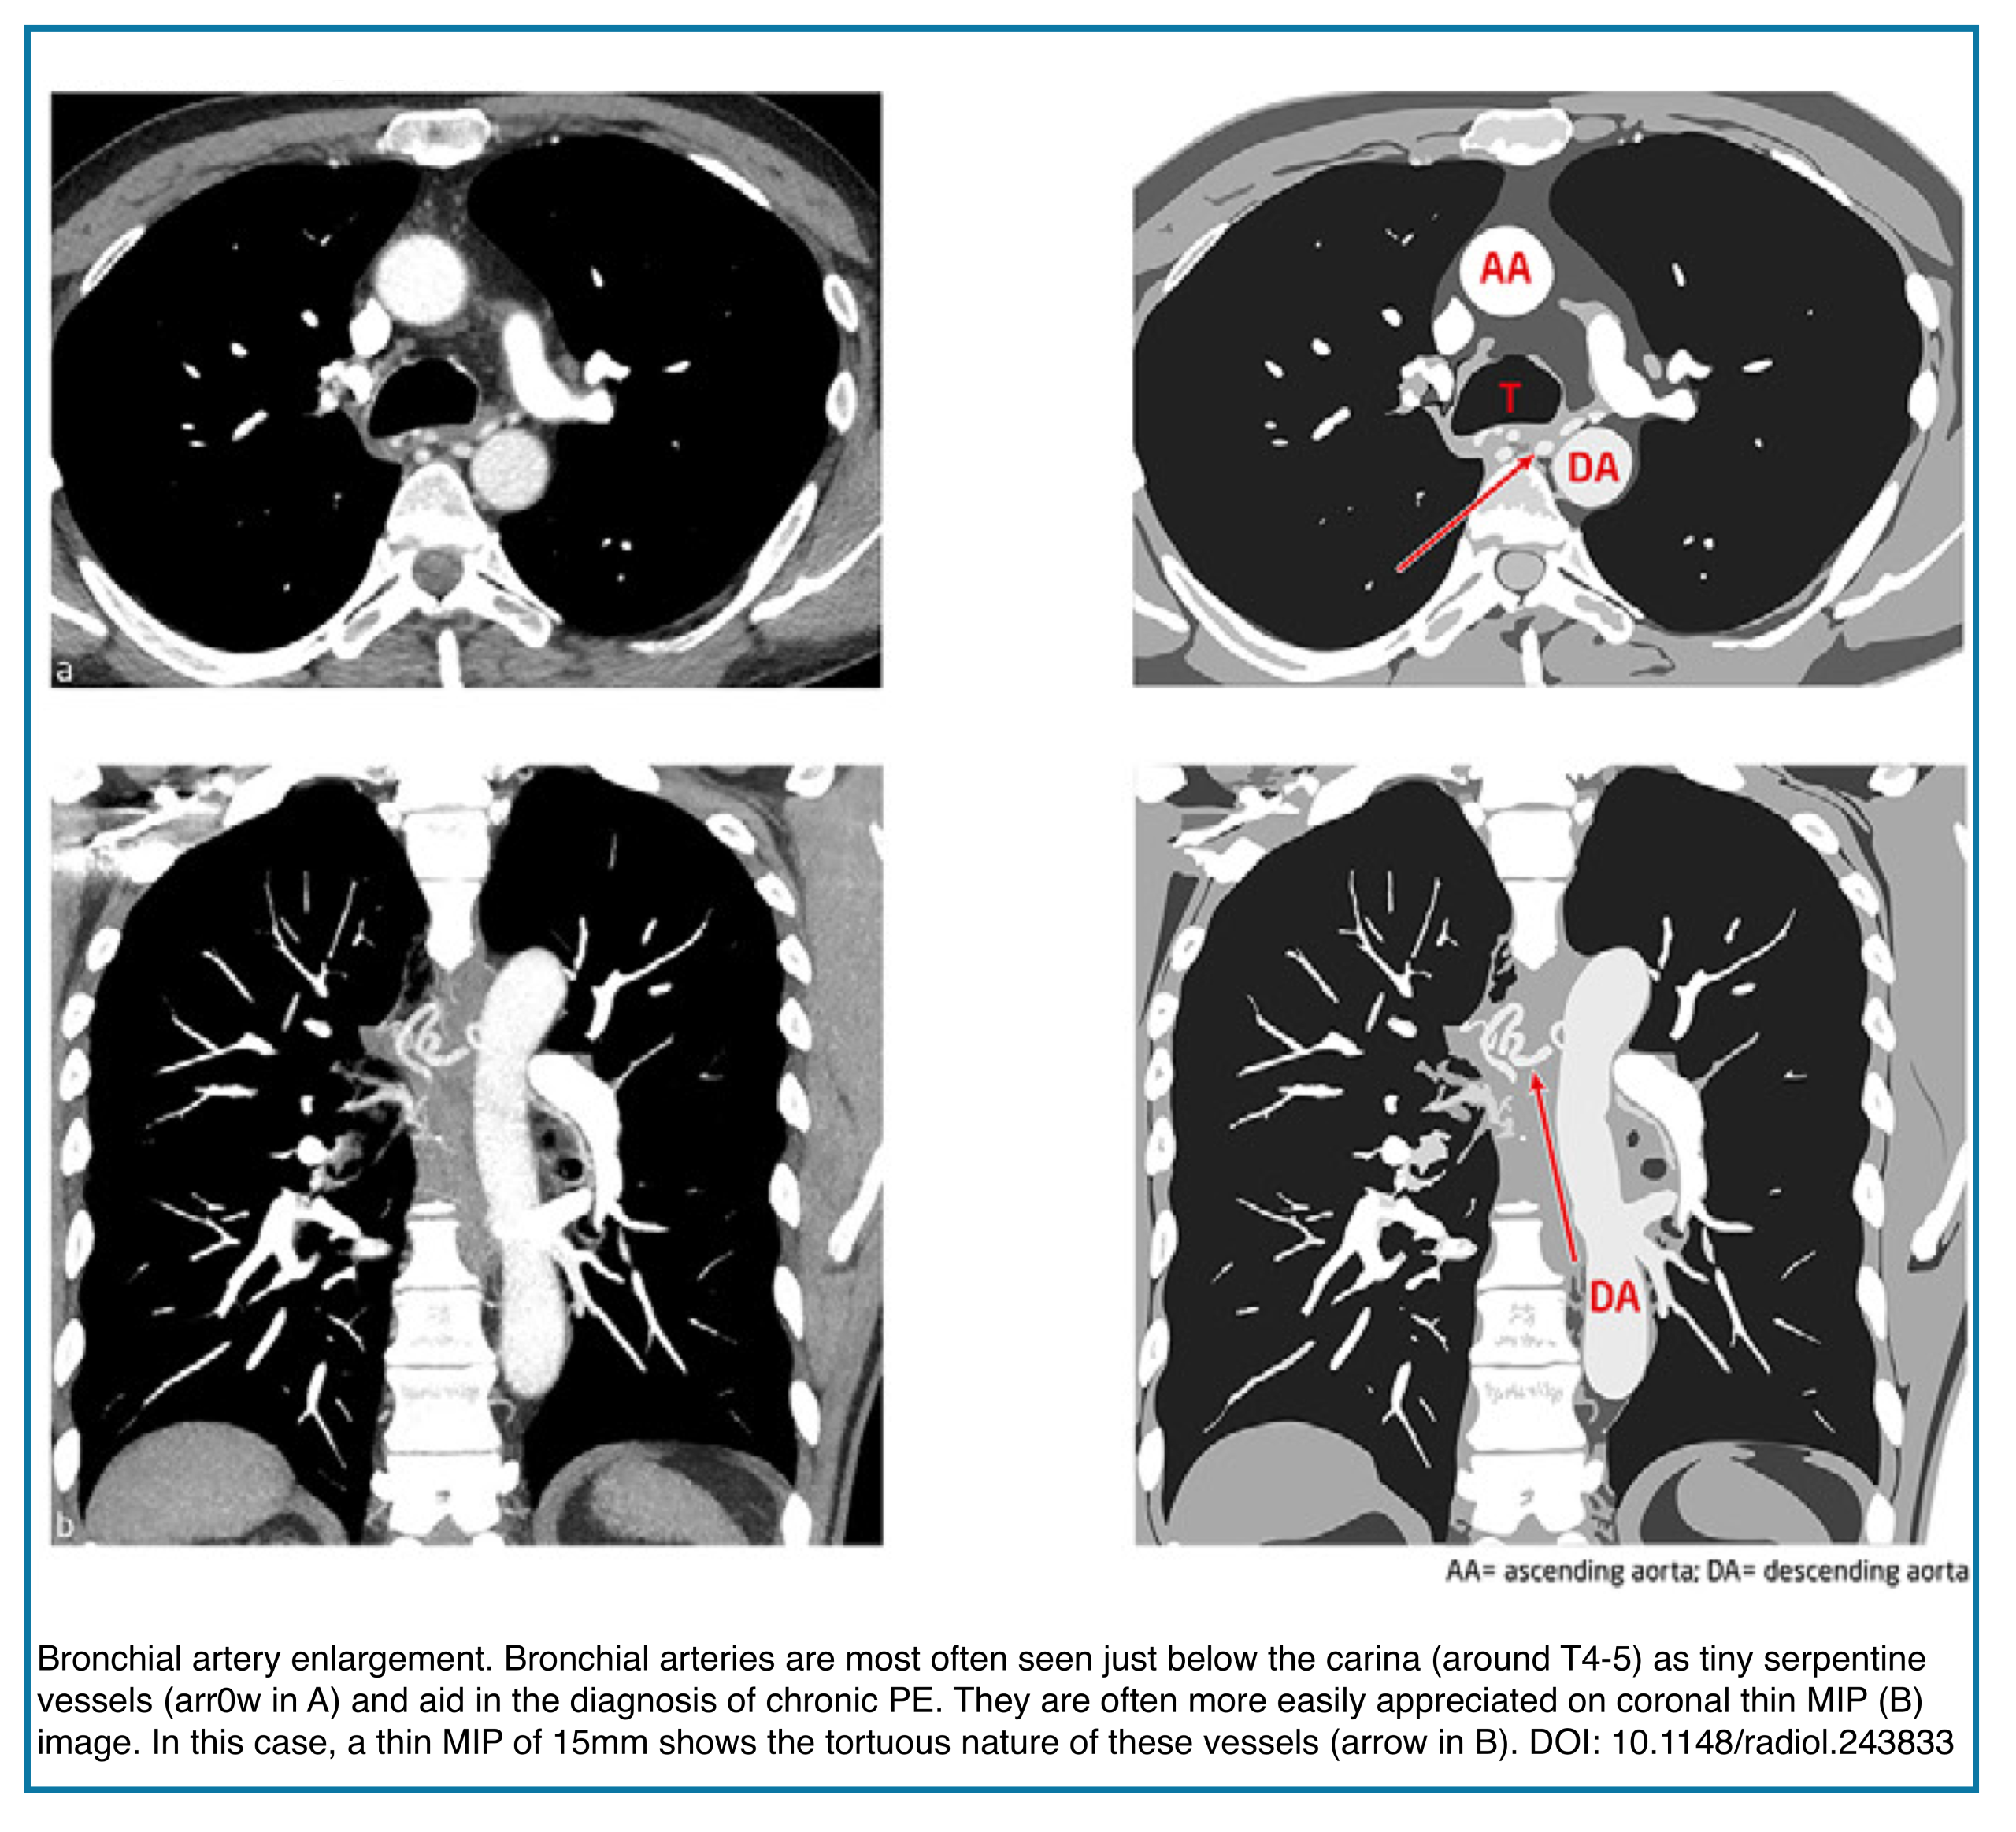

Enlarged Bronchial Arteries

Markedly enlarged bronchial arteries (>1.5 mm diameter in the mediastinum) are one of the most specific signs of chronic disease, indicating long-term compensation (Figures below).